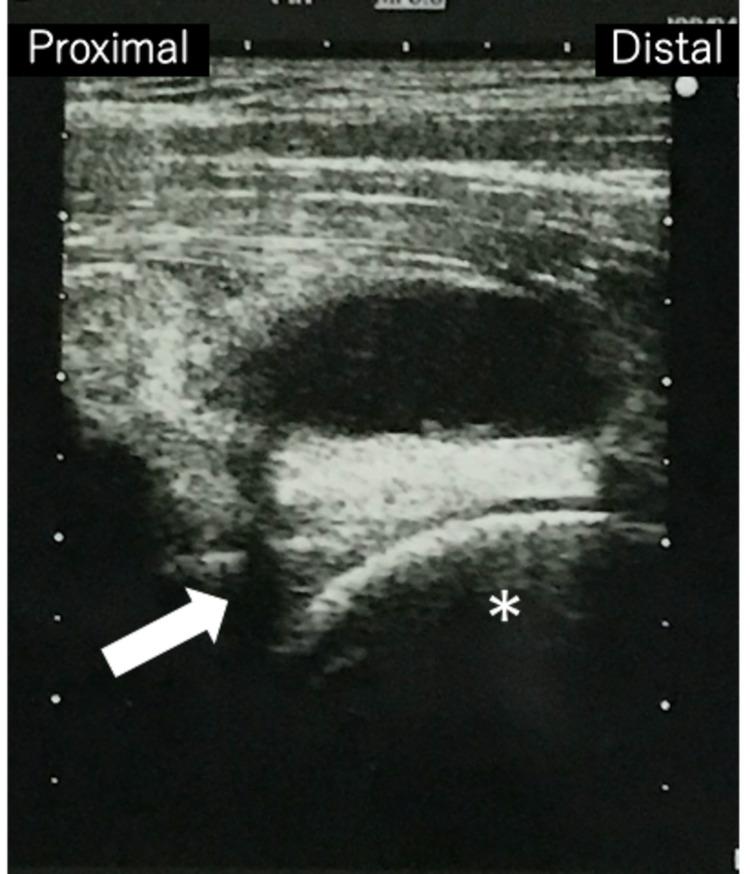

Iliopectineal bursitis usually develops subsequent to other hip pathologies and can often be treated conservatively. However, when conservative treatment fails or the enlarged bursa causes pain or compression of the surrounding neurovascular structures, surgery may be required. Most previous studies have described open surgeries, and reports on endoscopy are very limited. We present a case of iliopectineal bursitis associated with developmental dysplasia of the hip (DDH) that was successfully treated endoscopically. A 16-year-old female with a one-year history of right inguinal pain was referred to our department. She was diagnosed with a hip ganglion and treated with needle aspiration nine times by her previous doctor. Radiographs revealed bilateral DDH without narrowing of the joint space. Magnetic resonance imaging revealed a distinct mass in the deep layer of the iliopsoas muscle, and communication between the mass and the hip joint was observed on ultrasonography. Endoscopic debridement and resection were performed based on the diagnosis of iliopectineal bursitis. We partially debrided the medial side of the rectus femoris muscle toward the deep layer and resected the bursa. We observed a burst of concentrated content from the bursa and confirmed the disappearance of the mass by intraoperative ultrasonography. The postoperative course was good, and there were no functional restrictions or symptom recurrence at two-year postoperatively. Endoscopic resection for repetitive iliopectineal bursitis without an intraarticular procedure does not induce hip instability in patients with DDH and is a minimally invasive cosmetic procedure, and superior to open surgery, especially in young women.

髂耻滑囊炎通常继发于其他髋关节病变,且往往可采用保守治疗。然而,当保守治疗失败或肿大的滑囊引起疼痛或压迫周围神经血管结构时,可能需要手术治疗。以往大多数研究描述的是开放手术,关于内镜手术的报道非常有限。我们报告一例与髋关节发育不良(DDH)相关的髂耻滑囊炎,通过内镜手术成功治愈。一名16岁女性,有1年右侧腹股沟疼痛病史,转诊至我科。她曾被诊断为髋关节腱鞘囊肿,之前的医生对其进行了9次穿刺抽吸治疗。X线片显示双侧DDH,关节间隙无狭窄。磁共振成像显示髂腰肌深层有一明显肿块,超声检查发现肿块与髋关节相通。根据髂耻滑囊炎的诊断进行了内镜清创和切除术。我们向深层部分清创股直肌内侧,并切除滑囊。我们观察到滑囊中有大量浓缩物涌出,并通过术中超声确认肿块消失。术后恢复良好,术后两年无功能受限或症状复发。对于复发性髂耻滑囊炎,在内镜下切除而不进行关节内手术,不会导致DDH患者髋关节不稳定,是一种微创美容手术,优于开放手术,尤其对于年轻女性。